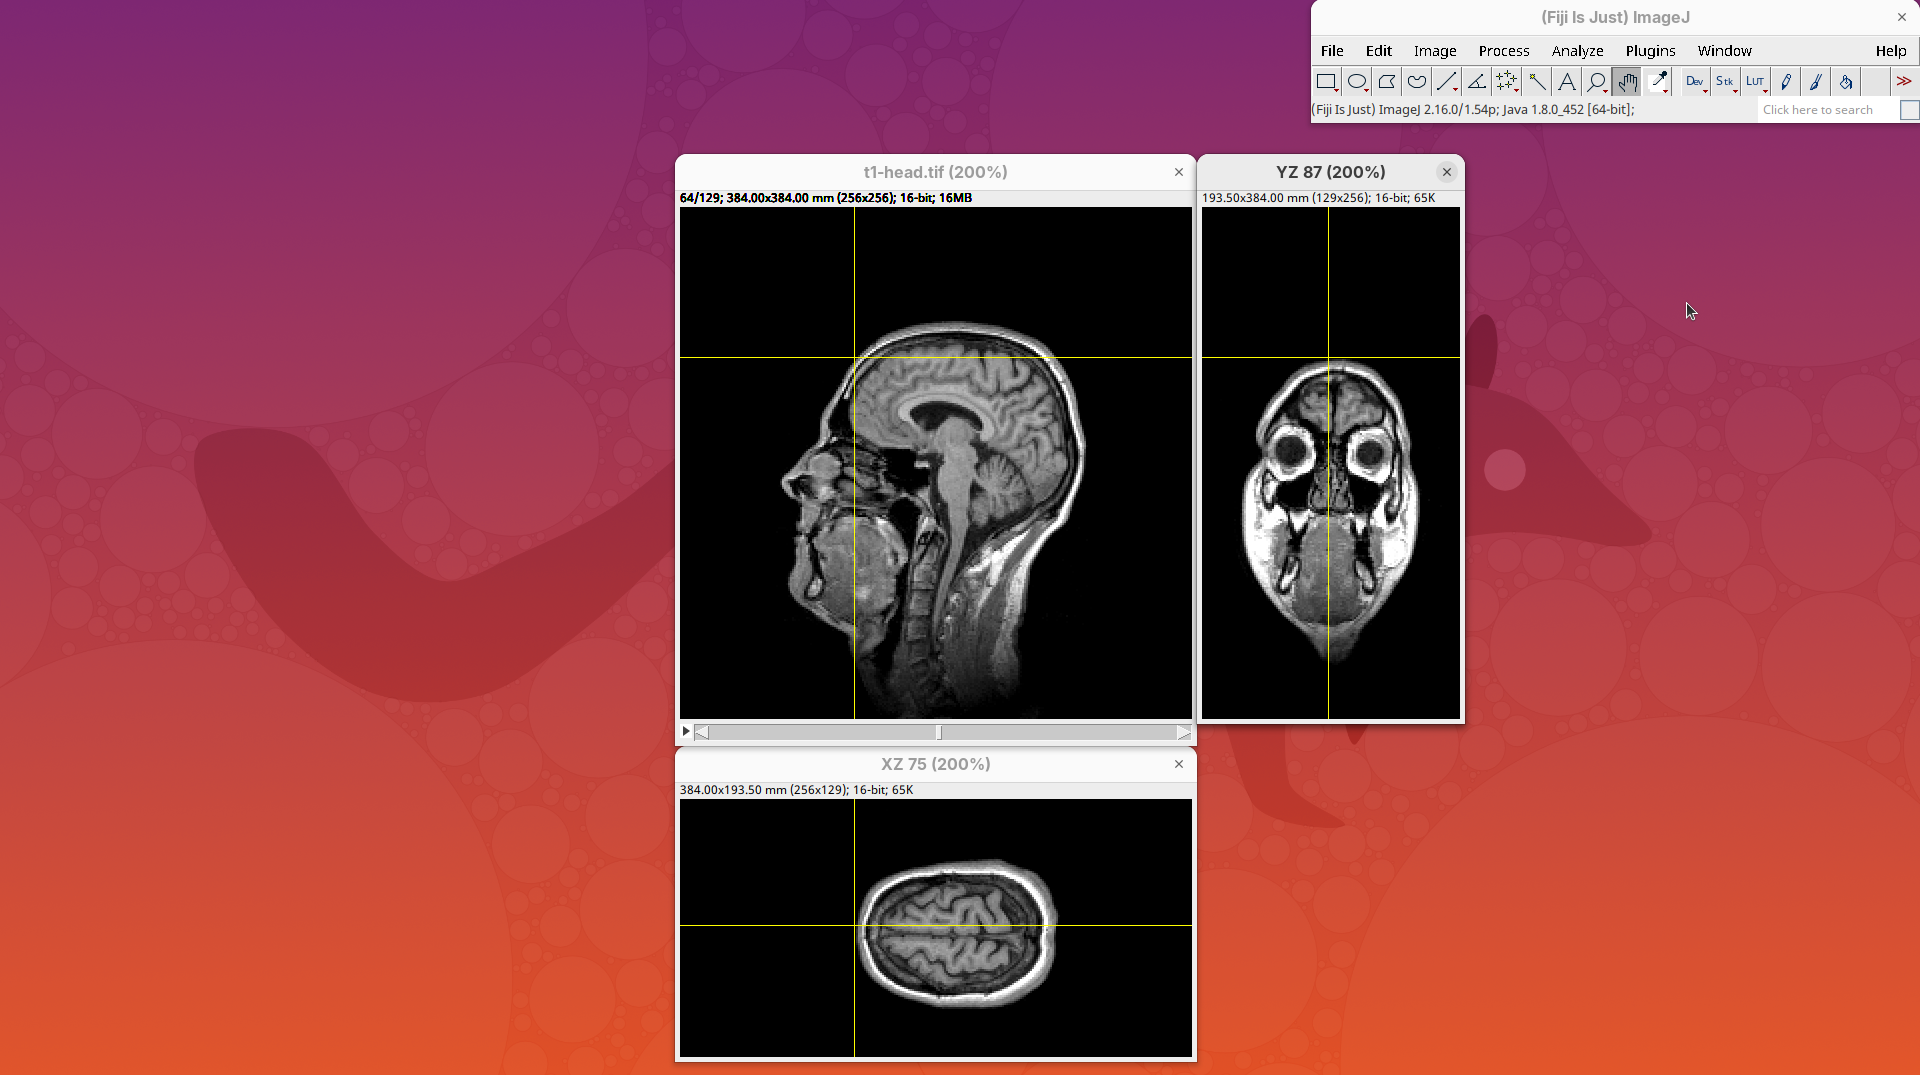

Orthogonal Views

Orthogonal Views is a tool that shows the optical sections through the orthogonal planes of XY: XZ and YZ. It is an easy and quick way to get a sense of the tridimensionality of your dataset. Whenever I’m opening a dataset for the first time I use Orthogonal Views. To activate it:

- Click on

Image>Stacks>Orthogonal Views(or pressCtrl+Shift+H). - The XZ and YZ panels will open next to your XY stack.

- The yellow lines are synchronized between the panels.

- Click around the different parts of the head to inspect the same position under different angles.

Orthogonal Views is a great way to start understanding your 3D data.